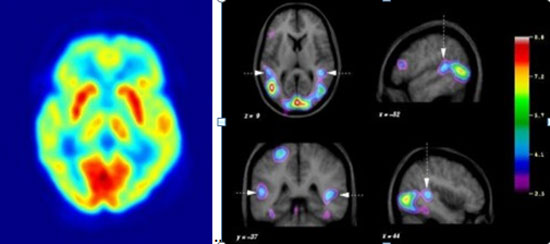

Plus précisément, en scrutant le cerveau de leurs volontaires via la technique de tomographie à émission de positons (TEP), l’équipe suédoise a mise en évidence le rôle de certains récepteurs chimiques, appelés 5HTIA. Situés sur une catégorie de neurones dits « sérotoninergiques », ces récepteurs ont l’art d’abaisser la quantité de sérotonine libérée dans le cerveau. Or, il est apparu que plus la quantité de ces récepteurs 5HTIA était faible, et donc plus le taux de sérotonine était élevé, plus la religiosité était avérée. C’est-à-dire que dans ce cas, « les sujets étaient enclins à appréhender les difficultés de la vie en développant l’idée qu’une présence divine existe dans le monde. Ils disaient également souvent avoir vécu des expériences mystiques. Ou bien encore, ils croyaient aux miracles ou à l’existence d’un sixième sens ». Ainsi donc, un taux élevé de sérotonine dans le cerveau accroîtrait le degré de religiosité !

Concrètement, ces recherches ont mis en évidence une zone corticale bien précise située dans la partie arrière haute du crâne : le cortex pariétal supérieur. Et pour cause : le fameux sentiment de fusion mystique d’avec le monde apparaît d’autant plus manifeste que l’activité de cette zone est ralentie. C’est une célèbre expérience d’imagerie cérébrale menée en 2001 par le neurobiologiste Andrew Newberg qui l’a démontré.

En analysant par TEP l’activation cérébrale de huit moines tibétains bouddhistes immergés, via une technique de respiration spécifique, dans un état de méditation connu pour déboucher sur cette sensation de symbiose, le neurobiologiste a découvert sur son écran un étrange phénomène : plus la méditation semblait profonde, plus la zone du cortex pariétal supérieur du cerveau… s’assombrissait. Signe d’une chute de l’irrigation sanguine, donc d’une baisse d’activité. Pourquoi cette zone ? Andrew Newberg a une explication : « L’une des fonctions du cortex pariétal supérieur est de permettre à l’individu d’effectuer la distinction entre son corps et l’environnement et de s’orienter dans l’espace. Ce qui expliquerait, lorsque son activité se ralentit, l’émergence d’altérations de la perception spatiale et de la sensation de fusionner avec l’Univers ».